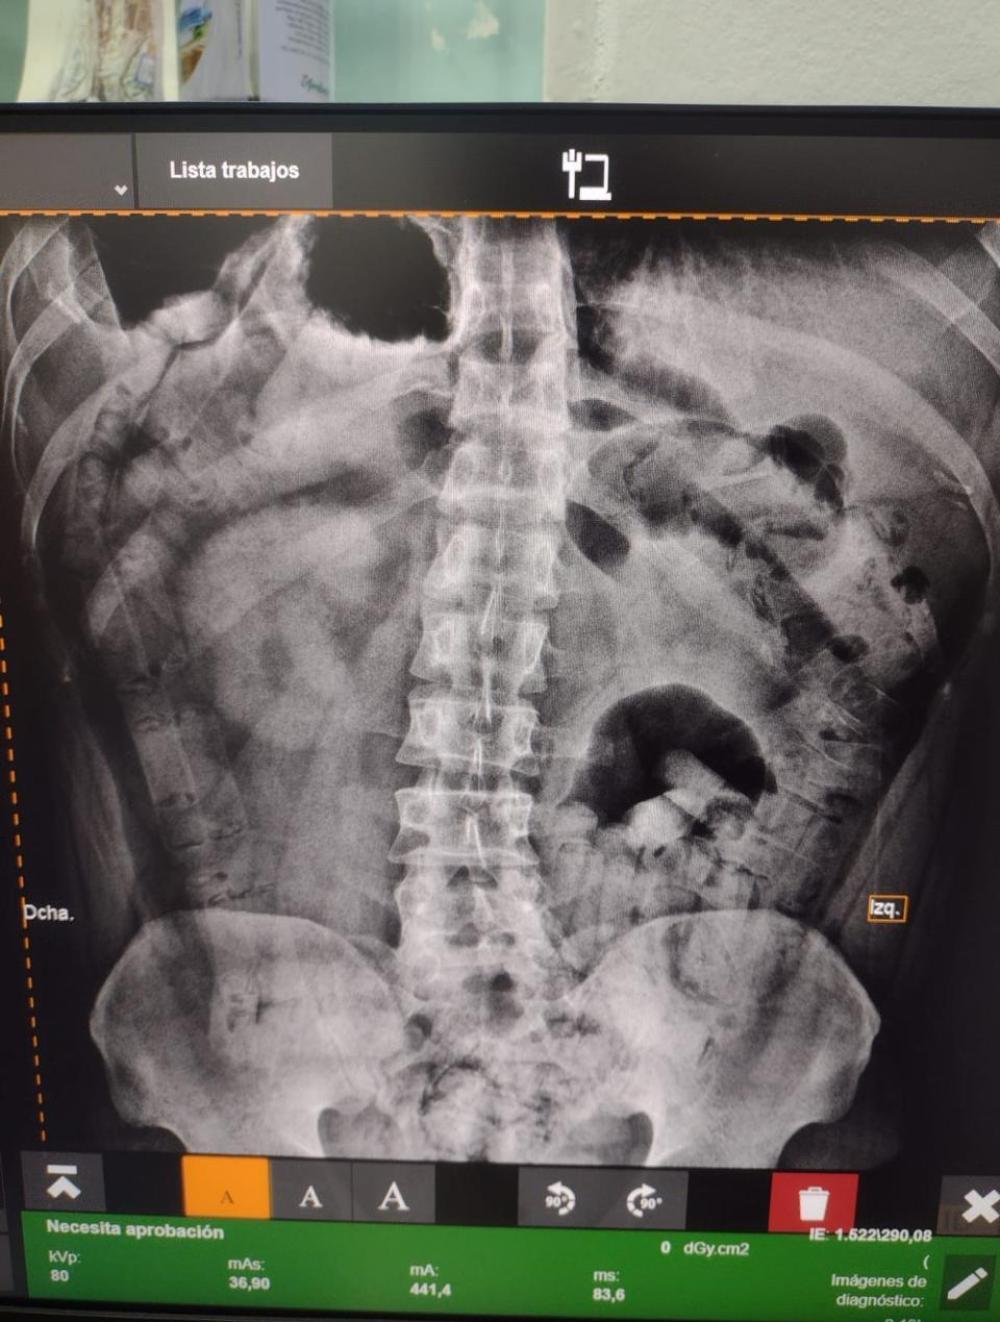

El Juzgado Federal de Tucumán ordenó el traslado de los individuos a un centro de salud, donde pruebas de rayos X revelaron cuerpos extraños en sus estómagos. Bajo supervisión médica, ambos sujetos expulsaron 206 cápsulas que contenían aproximadamente 2 kg de cocaína. Posteriormente, el Juzgado Federal de Tucumán ordenó la detención de los dos hombres.